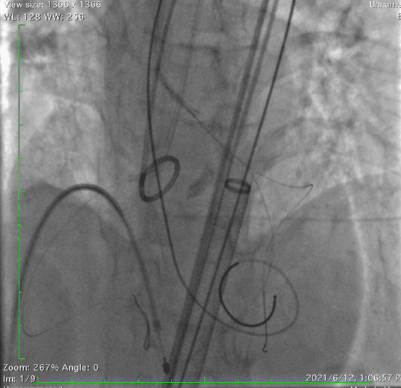

采用右冠guidezilla+预置支架保护,在右足Double-S体位下,选择Venus-A Valve 23瓣膜精准释放,跨瓣后及释放过程中患者持续低血压,释放2/3后血压仍无法恢复,调整好JR指引导管和guidezilla深度后,完全释放瓣膜。交换猪尾导管后复苏推药,患者血压逐渐恢复正常水平。

瓣膜释放后造影显示瓣膜定位准确,整个支架往右冠脉窦偏移,左冠显影正常,无遮挡。小心回撤guidezilla至冠脉口,JR指引导管内造影显示右冠脉遮挡仅留一条细线,决定植入烟囱支架,并充分后扩张。